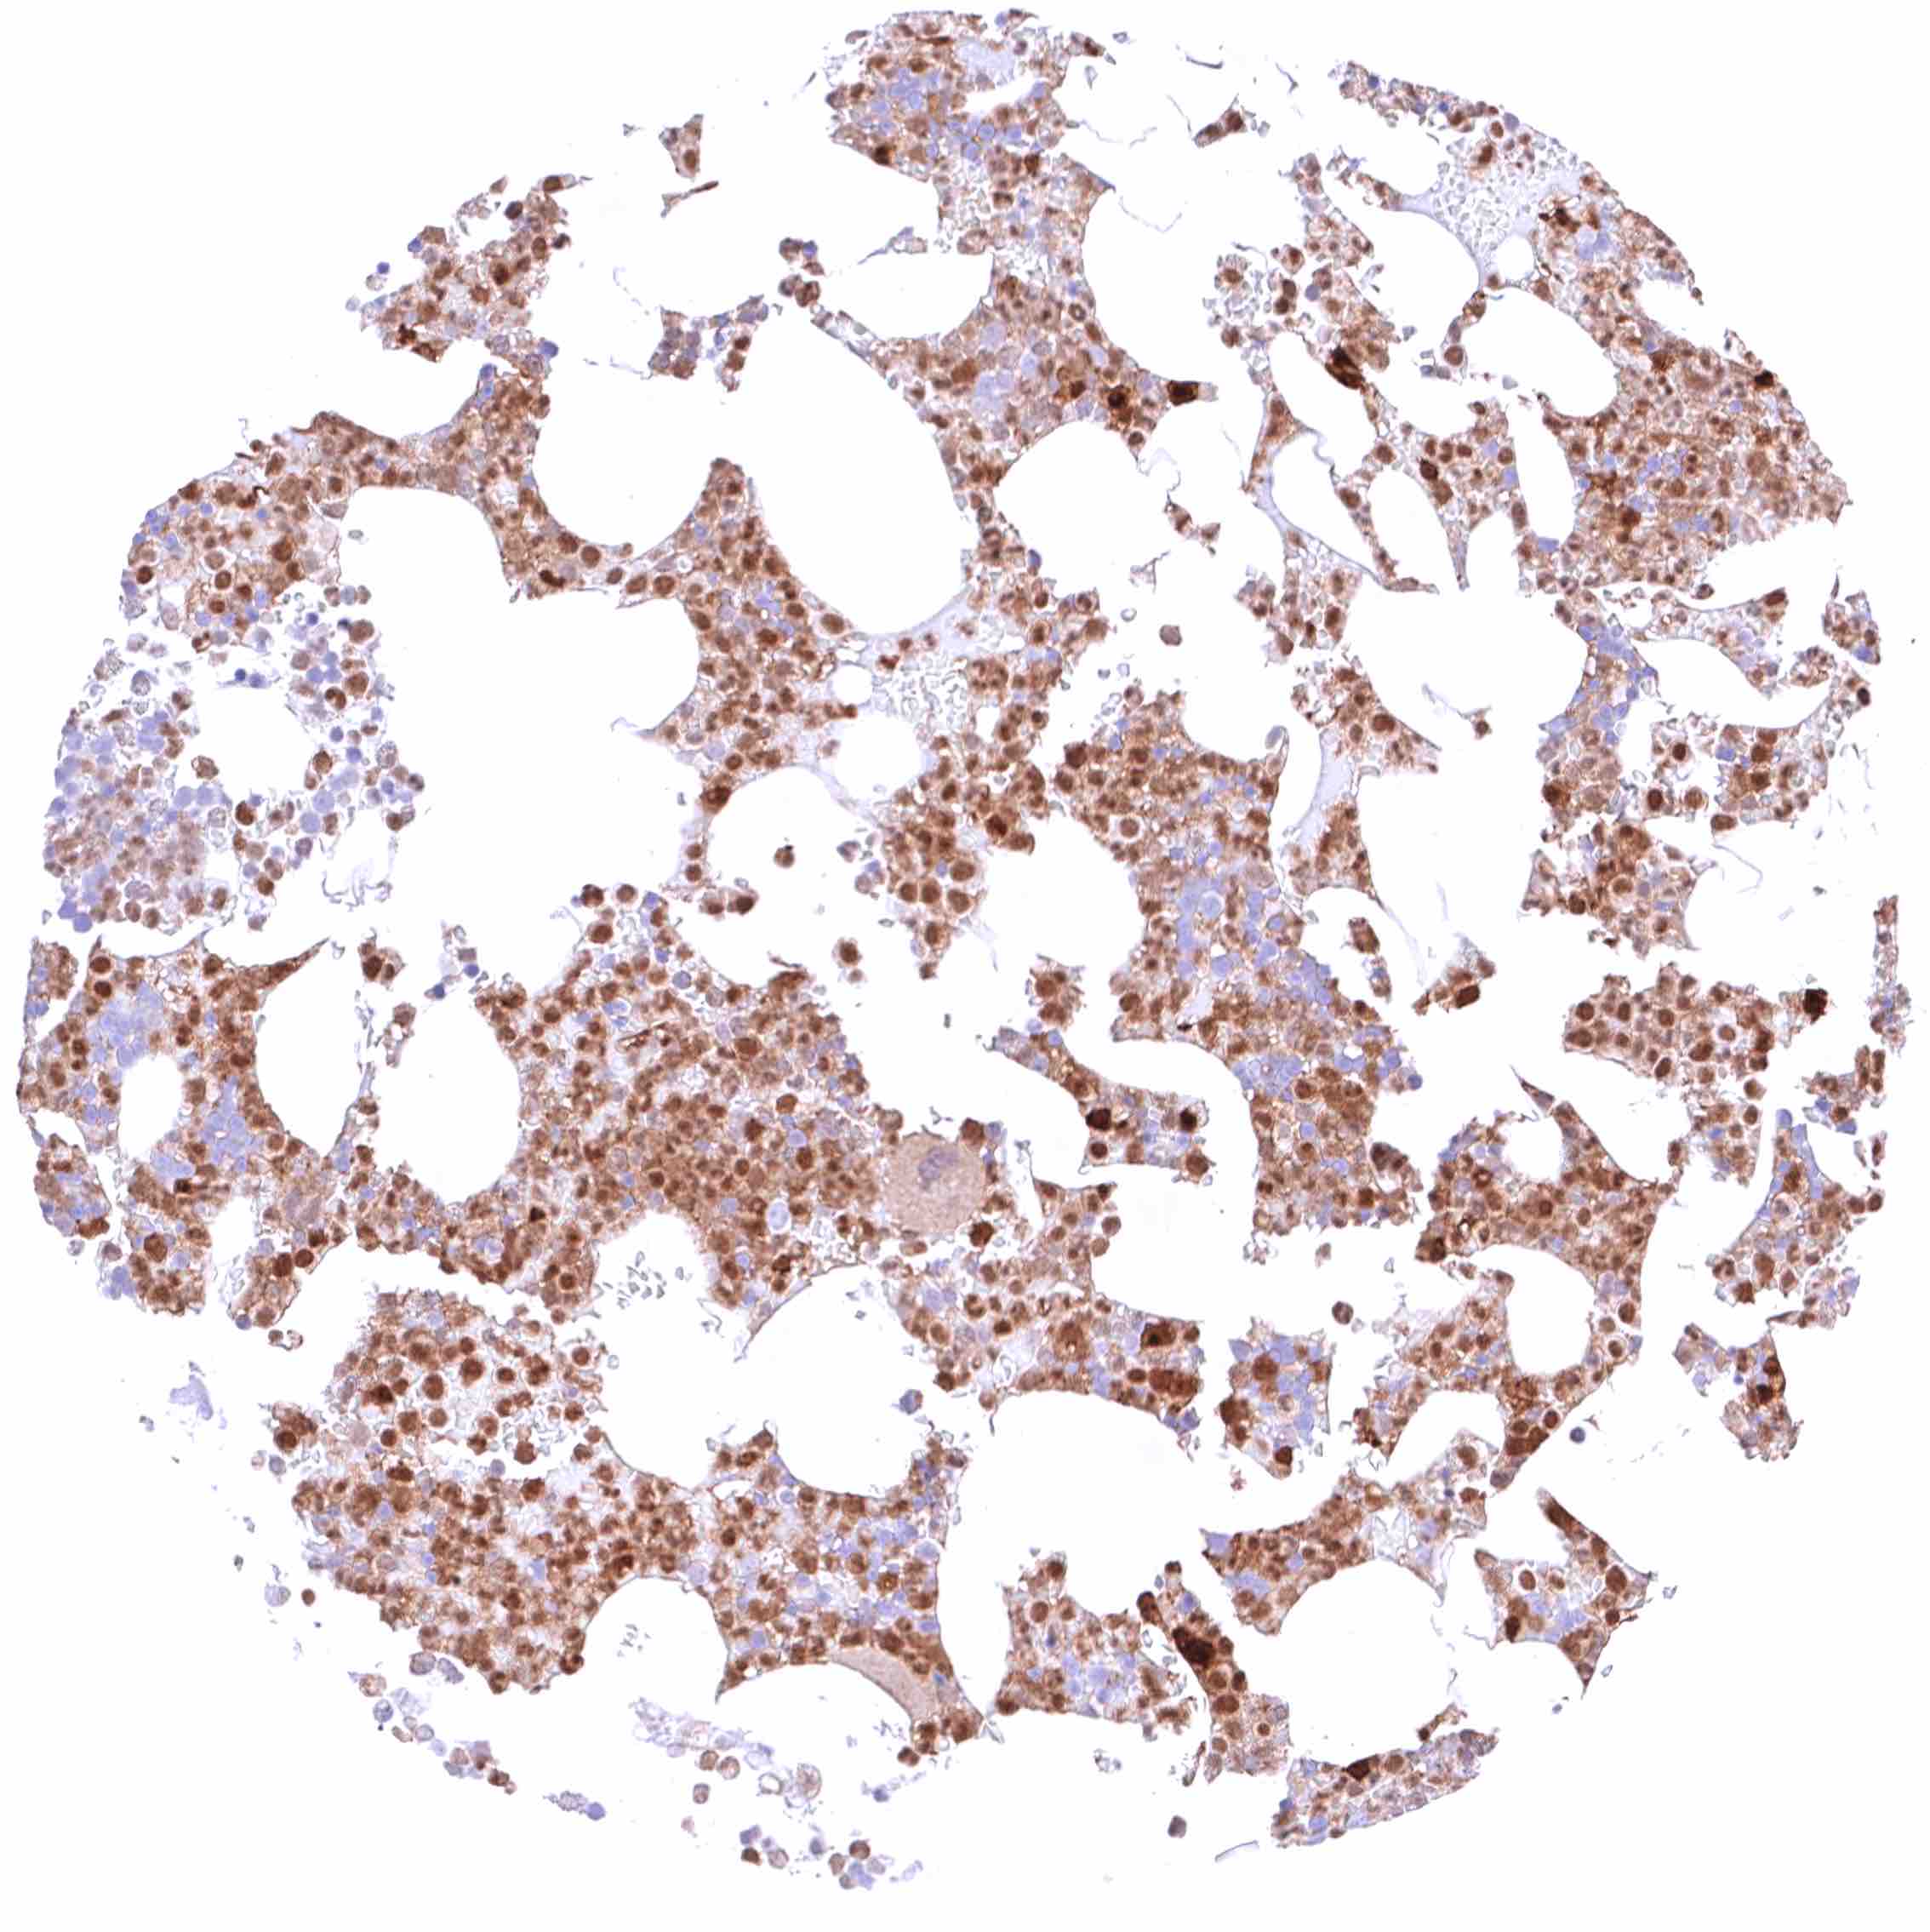

Lung – Moderate, predominantly cytoplasmic positivity of alveolar endothelial cells. Strong, nuclear and cytoplasmic GSTP1 positivity of at least a significant subset of alveolar cells.